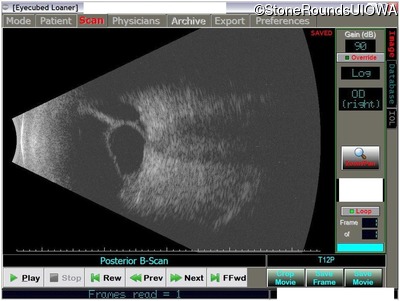

This 43 year old woman first experienced a slight loss of visual acuity at age 23. Fluorescein angiography at that time revealed some vascular leakage from the optic discs and peripheral retina. The maximum combined response of the ERG revealed a selective loss of the b-wave.

Age at visit: 43 years (Visit 2)